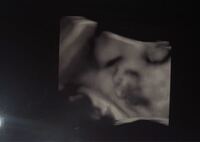

チャーミー小結さんの妊娠32週目のエコー写真 命の始まりは神秘的! 2D・3D・4Dのエコー写真で見る「私と赤ちゃんの実録260日」 妊娠32週目。 赤ちゃんの体重1915g。 この頃の楽しみは医師軍団による回診で、ドラマ「白い巨塔」の再現VTRを見ているようFeb 17, 16 · 妊娠32週目のお腹の大きさの写真&体重!!ますます便秘がひどくなる!!Sep 15, 17 · 妊娠32週目(32w0d~6d)のエコー写真とエピソード|妊娠9ヶ月 妊娠32週目は、妊娠9ヶ月の第1週目です。

妊娠32週 4dエコーで胎児の顔がわかる ちわさんぽ At Malaysia Kuala Lumpur